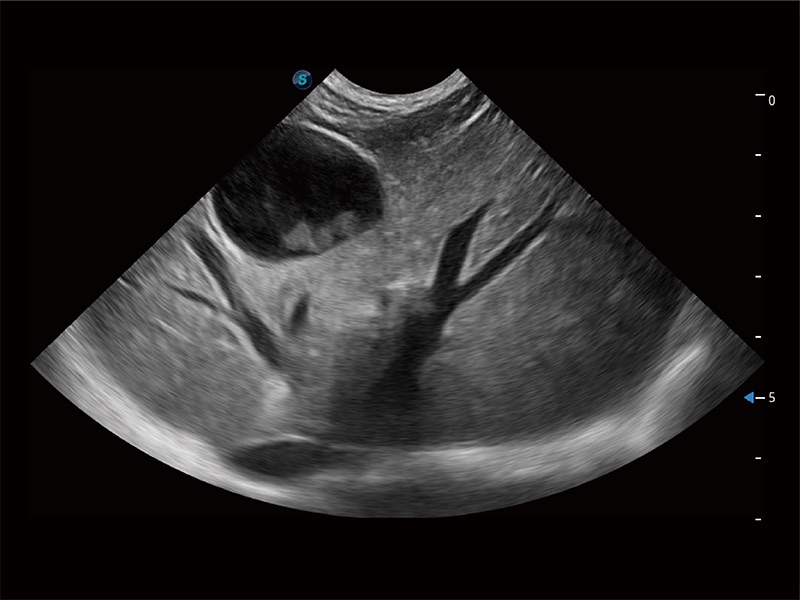

动物是人类最亲密的朋友和最值得信赖的伙伴。米兰官方网站也一直致力于探索动物专用的超声影像解决方案。全新推出的ProPet系列,是米兰官方网站在动物超声影像智能化、专业化、精准化的一次跨越式革新。动物不能用言语来表述自己的不适,通过超声影像,ProPet系列搭建了动物医生与不同物种沟通的“桥梁”,为动物医生注入了“治愈之力”。 ProPet 80 是米兰官方网站匠心打造的一款高端动物专用彩超,采用性能卓越的全新硬件架构,极大提升超声系统的运行效率和数据处理能力,帮助动物医生从容应对日益增多的挑战性病例和日益多样化的临床需求。

高性能和先进的临床应用工具可以为动物医生提供临床信心。ProPet 80 搭载了先进的腹部和浅表应用工具,帮助医生在日常临床实践中发挥前所未有的作用。

ProPet 80 全新的动物超声智能软件和丰富的探头群,为动物医生提供了高清晰度和精细分辨率的图像,无论在宠物、马科、畜牧还是实验室动物等应用中都可以轻松应对,为您的日常工作带来满意的体验。